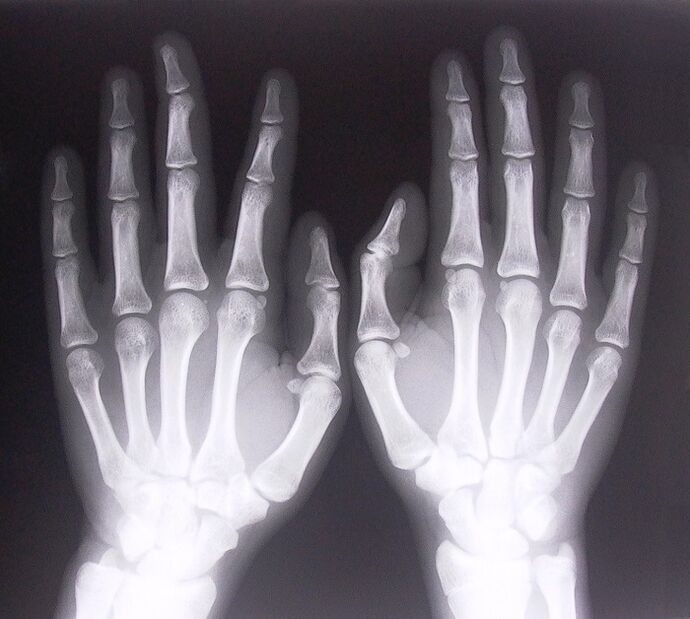

- Stenosing ligamentitis.To identify the cause of the disease, it is necessary to undergo an X-ray.Symptoms are typical: painful movement of the hand, loops of the clenched palm.Even during extension, a normal click is heard.

- Take x-rays.